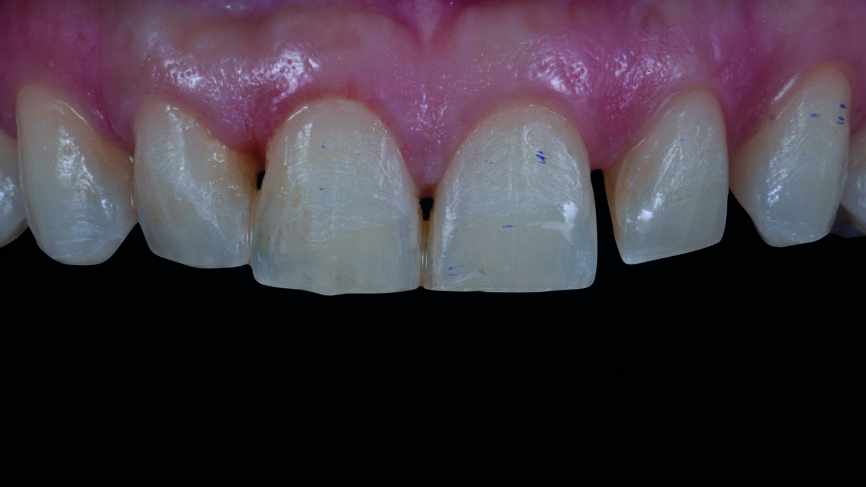

| Fig. 15a : Facettes en céramique feldspathique avec pâte d‘essai

Fig. 15b : Facettes réalisées en technique CFAO avec pâte d‘essai.

| Fig. 15c : Facettes en céramique feldspathique du premier quadrant et simultanément, facettes réalisées en technique CFAO du second quadrant avec pâte d‘essai.

Le jeu de facettes en céramique feldspathique a été fabriqué en IPS Style (Ivoclar Vivadent) sur un modèle en plâtre-pierre, tandis qu‘un bloc IPS Empress CAD Multi (Ivoclar Vivadent) a été utilisé pour le jeu numérique (Figs. 13 et 14). Les deux jeux ont été évalués en bouche avec une pâte d‘essai afin de comparer les propriétés optiques des facettes feldspathiques et des facettes réalisées en technique CFAO (Figs. 15a–c).